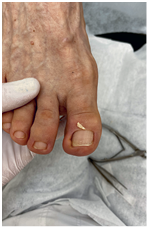

Хирург не заботится об эстетической стороне вопроса. Ему важно решить проблему, чтобы вы больше не испытывали дискомфорт. Часто после хирургического лечения ноготь меняет форму, становится менее красивым – к этому нужно быть готовым.

Иллюстрация к книге — Подология понятно. Важен каждый шаг. Справочник по проблемам подологии для клиентов и мастеров эстетики [i_269.jpg]

Иллюстрация к книге — Подология понятно. Важен каждый шаг. Справочник по проблемам подологии для клиентов и мастеров эстетики [i_270.jpg]

Иллюстрация к книге — Подология понятно. Важен каждый шаг. Справочник по проблемам подологии для клиентов и мастеров эстетики [i_271.jpg]

Иллюстрация к книге — Подология понятно. Важен каждый шаг. Справочник по проблемам подологии для клиентов и мастеров эстетики [i_272.jpg]

Результат работы за 5 месяцев: подолог использовал крючковые коррекционные системы, а хирург сделал пластику внутреннего бокового валика (из-за хронических воспалений боковой валик стал гипертрофированным и давил на ноготь, от чего клиент испытывал постоянный дискомфорт)